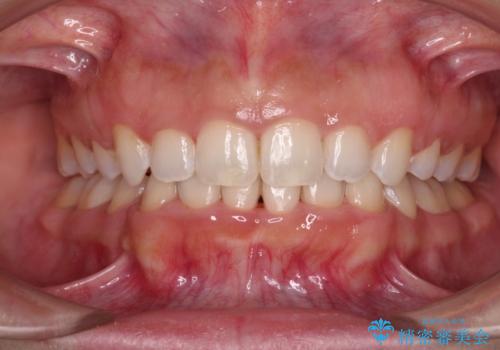

上下顎ともに前突しており、特に上顎は著しい突出感でした。

また、下顎歯列には左右差があり、非対称な抜歯が必要と判断されたため、治療は困難なものとなりました。

それでも根気強く通院してくださり、横からの顔貌の印象が大きく改善され、スムーズに口が閉じられるようになりました。